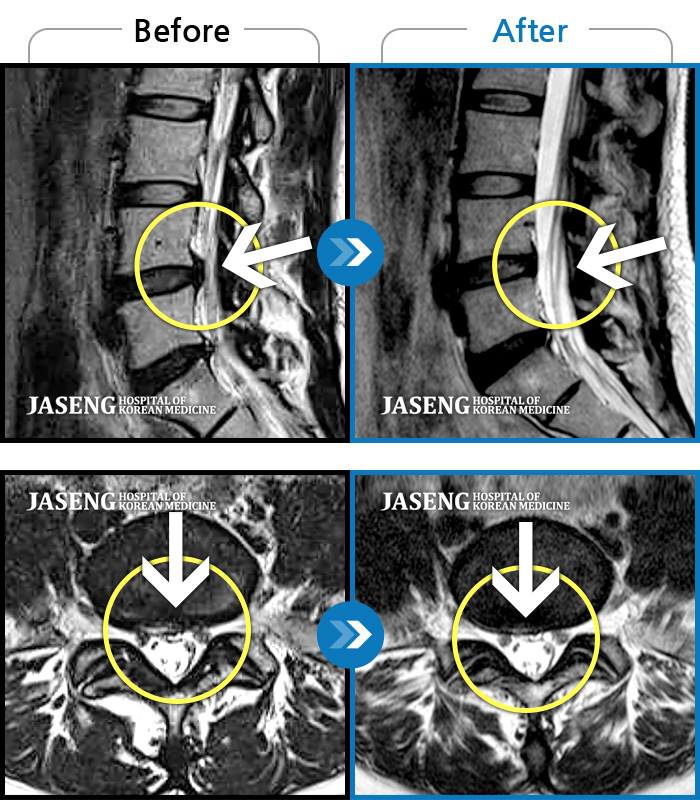

원장님이 차분하고 전문성 있게 환자 진료를 해주셔서 치료 받는 내내 마음이 편안했습니다. 디스크 파열이 나을 수 있을 지 의문이었는데 생활을 하는 데에 지장이 없도록 해주셔서 만족도가 높습니다. 감사합니다.

디스크 탈출로 인해 다리저림 통증있어 여러병원 찾아서 치료를 받았지만 호전이 없어 한병병원으로 오게 되었습니다 시간에 구애 없이 설명을 친절히 잘 얘기 주셔서 믿고 입원 결정을 했습니다 .^^ 좋은결과로 기대하며 치료받고 있습니다

퇴원을 하루 앞두고 있는 환자입니다. 디스크로 인해 통증으로 인해 두려움과 걱정이 많았으나 원장님의 친절한 설명과 적극적인 각종 치료로 인해 빠른 회복과 건강을 다시 되찾아서 매우 기쁩니다. 많은 타 병원 다르게 진료시 제 상해에 대해 친절한 설명으로 이해가 쉬웠으며, 따뜻한 말투로 심신까지 안정될 수 있게 많은 도움을 주셨습니다. 역시 척추는 자생한방병원이라고 느끼는 치료기간이였으며, 다시 찾아오고 싶은 병원 및 원장님에게 감사드립니다.